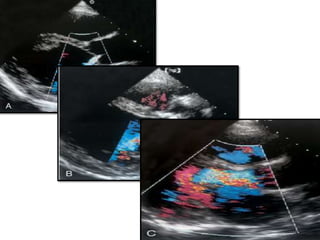

Vena contracta

• <0.3cm mild

• 0.3-0.6 – moderate

• >0.6 - severe

Jet area

• In PSax view

• Using color doppler

• Compared to LVOT area

Height of AR jet

• From parasternal long axis view – the height of the jet just below

the valve can be measured using electronic calipers.

• Dimension expressed as the percentage of LVOT dimension to

provide an estimate of severity.

Jet height/outflow tract dimension ratio.

• Greater the percentage – the more severe the regurgitation.

• A jet that occupies more than 60% of the LVOT(either height or

area)usually indicates severe AR.